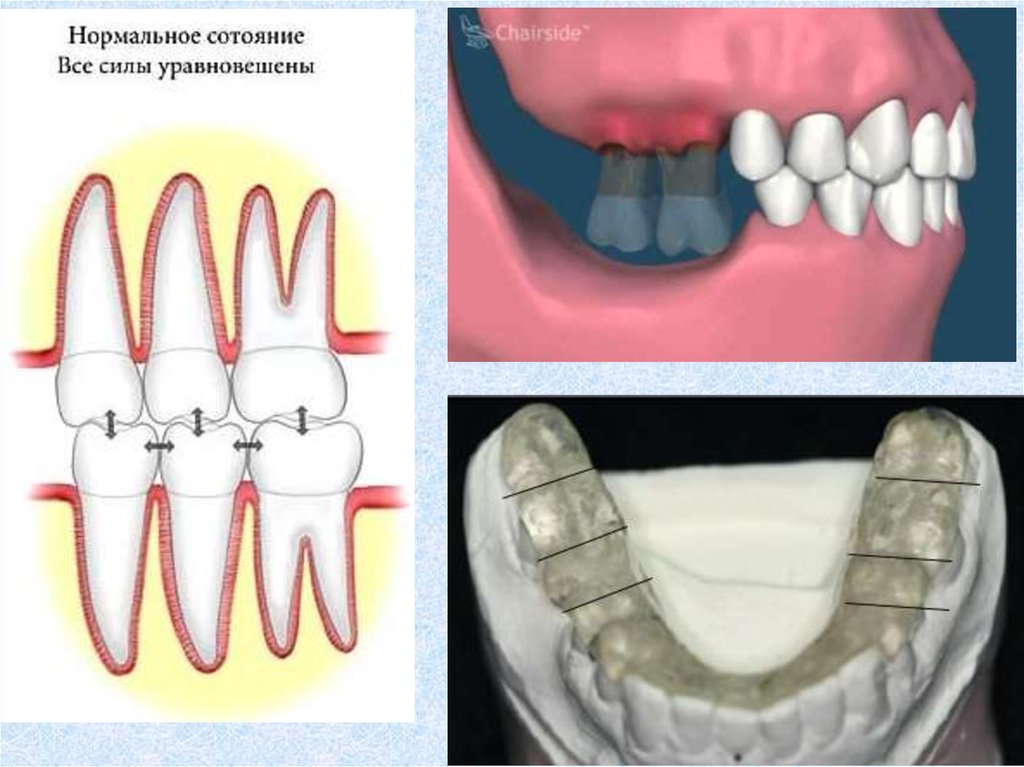

Рекомендации по профилактике

каппа на ночь мичиганская

контроль при дневной парафункции

Все стоматологи обязаны понимать суть нормального

функционирования диско-мыщелкового и жевательного

мышечного комплекса, а также уметь диагностировать

РВНЧС